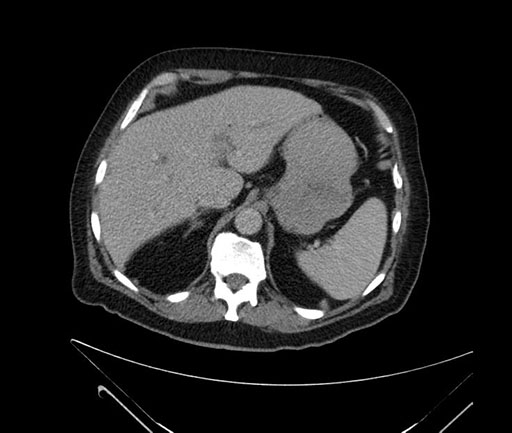

Whipple (pancreaticoduodenectomy) [case 7]

Imaging Analysis

Look through the patient's CT scan to identify any areas of concern for the necessary procedure.

Coronal - stented